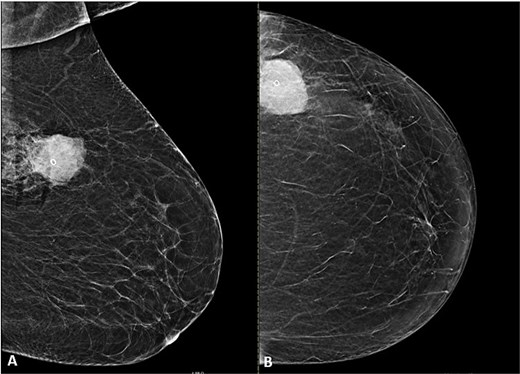

Breast ultrasound showed a fatty background with a 3.6 × 3.3 × 3.0 cm round, heterogeneous hypoechoic mass at 2 o’clock with indistinct margins and internal vascularity, and a single prominent but benign appearing left axillary node (Fig. 1A and B). Mammography revealed almost entirely fatty parenchyma (ACR A) with a hyperdense left upper outer quadrant mass, without calcifications or architectural distortion (BI-RADS 4C on the left, 1 on the right) (Fig. 2A and B).

Mammogram of the left breast. (A) Craniocaudal (CC) and (B) mediolateral oblique (MLO) views demonstrate a high-density, microlobulated mass containing a post-biopsy clip with surrounding post-procedural changes.